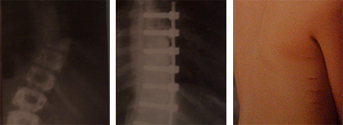

Fractura vertebral por estallido, inestable,

con un índice sagital (cifosis) no tolerable

Imagen de la fractura y del postoperatorio con una reducción anatómica

y una visión de la espalda de la paciente con incisiones puntiformes

a las 48 horas de la intervención, en el momento de recibir el alta.